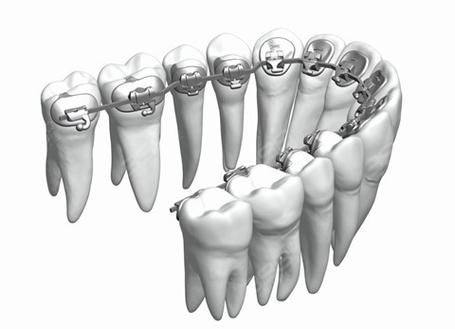

牙齿矫正:涵盖舌侧矫正、隐形矫正、金属自锁托槽矫正等多种技术,由经验多的正畸医师坐诊,可根据患者面部五官协调程度定制个性化方案,数字化模拟矫正成效,能解决牙列拥挤、龅牙、地包天等多种复杂正畸问题。

吴燕燕:执业医师,从事牙科诊疗工作10多年,拥有同济大学正畸学硕士学位,擅长舌侧矫正、隐形矫正、金属自锁托槽矫正、金属非自锁托槽矫正,曾在公办口腔医院执医多年,成功完成数千例牙齿矫正病例,是隐适美讲师、舌侧矫正明星医生。

杨广媛:主治医师,口腔正畸学硕士,擅长处理牙列拥挤、牙列稀疏、龅牙、牙齿不齐、下颌后缩等复杂口腔问题,精通舌侧矫正、颌面正畸、隐形矫正等技术,尤其擅长使用金属自锁托槽和陶瓷自锁托槽。

李华美:主治医师,擅长牙列拥挤、龅牙、地包天、牙齿不齐、下颌后缩等问题的矫正,精通牙齿早期矫治、乳牙间隙管理、隐形矫正、金属自锁托槽矫正、陶瓷自锁托槽矫正,专注提升患者口腔健康与牙齿美观度。